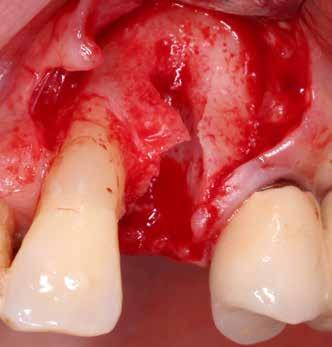

A foggyökér óvatos, atraumatikus eltávolítását követően excochleáltuk a parodontális és periapikális gyulladásos folyamatok eredményeként jelen lévő sarjszövetet. Az alapos tisztítás és a bukkális csontfal hiánya miatt indokolt membrántechnika megfelelő kivitelezése céljából mukoperioszteális lebenyt képeztünk, a lebeny tervezésénél arra törekedtünk, hogy az a lehető legkisebb méretű legyen és a második kisőrlő fog helyén lévő implantátum hámtapadását ne érintse, illetve, hogy lehetővé tegye a szemfog parodontális kezelését is (3., 4. ábra). Az alveoláris csont megőrzésének és regenerációjának segítése céljából a fog eltávolításával egy időben alveólus prezervációt végeztünk Stikcy Bone™ és PRF membránok segítségével, melyek előállításánál követtük a J. Choukroun által megadott vérvételi és centrifugálási protokollt (20). Kizárólag Process for PRF Duo Quattro System eszközöket, centrifugát, vérvételi egységet és csöveket, a membránok előállításához PRF Box-ot használtunk. Az A-PRF és S-PRF csöveket a PomPac eljárásnak megfelelően 4 °C-ra előhűtöttük. A Stikcy Bone™ készítmény előállításához Purgo™ xenografot használtunk. Az alveolust a grafttal feltöltöttük, tömörítő műszerrel enyhe kompreszsziót, illetve vertikális irányban 10 százaléknyi túlkompen-

zációt alkalmaztunk  (5., 6. ábra). Ezt követően a palatinális marginális gingivát óvatosan alápreparálva a bukkális defektust, valamint az okkluzális felszínt keresztirányban

A-PRF membránokkal borítottuk (7. ábra). A mukogingivális lebenyt – annak megnyújtása nélkül – a helyére fektettük és varratokkal rögzítettük, per primam sebzárást nem végeztünk (8., 9. ábra). A varratokat 2 hét után távolítottuk el, a varratszedésig a sebgyógyulás támogatására per os 1000 mg/nap C- és 12 000 NE/nap D-vitamint adtunk (20). A műtéti beavatkozást 24 hét gyógyulási időszak követte, melynek során sem helyi, sem gyógyszeres kezelés nem történt, az esztétikum javítása érdekében a páciens ideiglenes kivehető fogpótlást használt. A csontos gyógyulás ellenőrzése és az implantáció tervezése céljából állcsonti CT felvételt készítettünk, illetve lenyomatvételt végeztünk. A CT felvételen tökéletes csontos gyógyulást észleltünk, az alveolaris csont volumene teljes mértékben megtartott volt (10. ábra), a klinikai kép is ennek megfelelően alakult (11., 12. ábra)